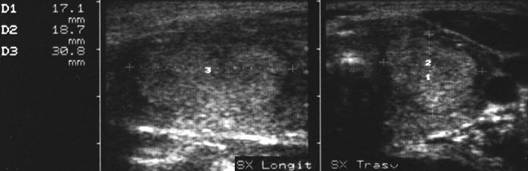

Femeie 25 ani. Nodul unic in lobul stang, contur net, hipoecogen, respecta parenchimul din jur, neomogen, de 18x23x36 mm (7,5 cc).

Citoaspiratia cu ac subtire: nodul adenomatos.

Examen histologic postoperator: adenom trabecular fetal.

Acelasi caz. La doppler color - vascularizatie interna, mai evidenta in powerdoppler.